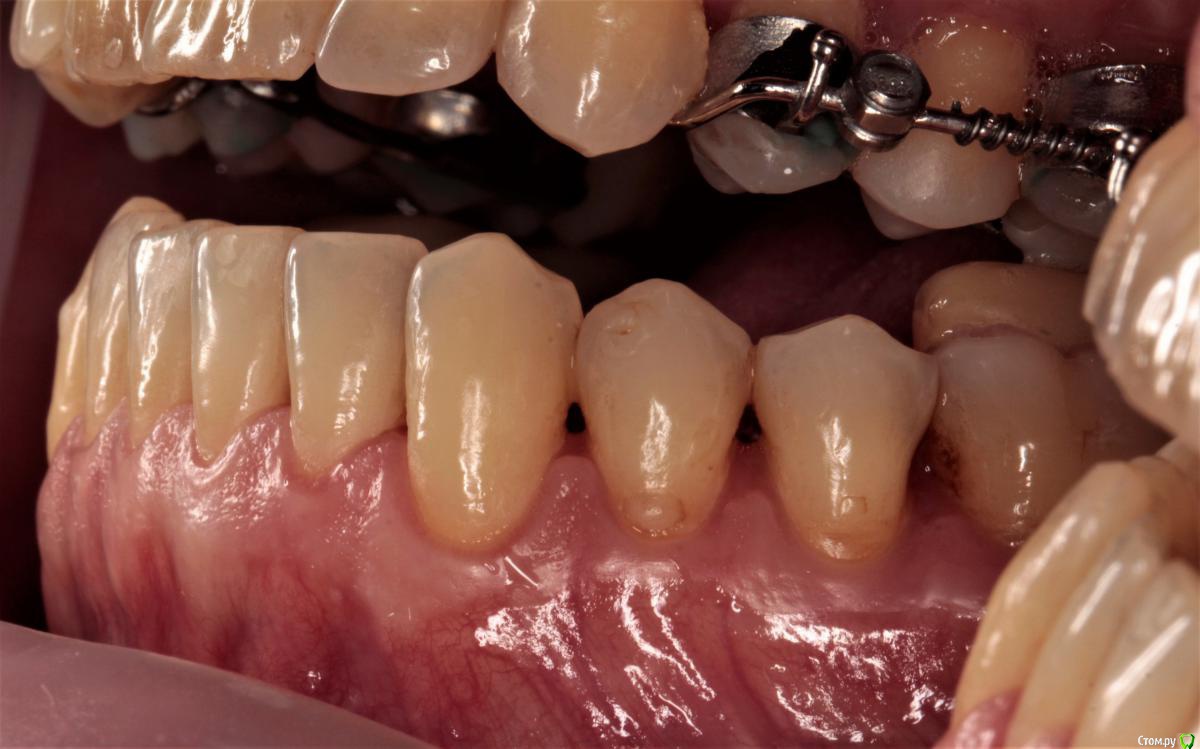

1. рецессии, клиновидный дефект, ВНЧС в результате неправильного прикуса (макрогнатия нижней и микрогнатия верхней челюсти)

2. год назад у меня был гингивит, переросший в некроз, приведший к полной потере сосочков нижней челюсти

так же мы понимаем, что сосочки это не только эстетика, но и важный функционал всей системы. И без них жить нельзя. При этом, технологии их восстановления, после некроза, не существует.

сосочки утеряны вследствие пародонтита. Восстановить их почти нереально. Только ортопедически, изменив форму зубов.